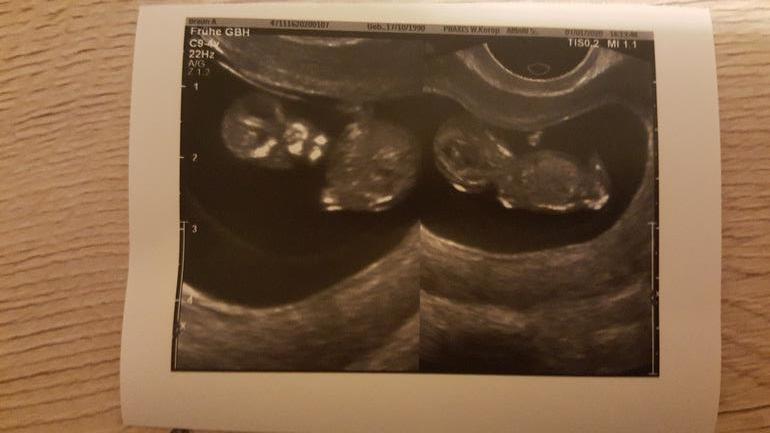

Это был первый сумбурный скрининг в моей жизни, где мне ничего не сказали кроме самого главного: ребеночек развивается в срок и выглядит все хорошо. Но в этот раз УЗИ делалось необычно долго. Показалось, что сам врач любовался)) И я да, пустила слезинку от умиления, когда увидела как он или она там толкается и крутится. Кстати муж был со мной😊 Сегодня у моего гинеколога было хорошее настроение и он был невероятно сговорчив, что "предположил" по половому бугорку мальчишку, но добавил: " На таком сроке я могу вас жестоко обмануть." Так что ждем 16 недель😁

Ну и покажемся на последок:

Блин ну инопланетянин же маленький🙈😁